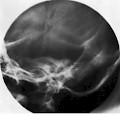

1. Felsenbein nach Stenvers

Früher wurde diese Technik angewendet, um den oberen und horizontalen Bogengang des Gleichgewichtsorgans (Vestibularapparat), die Hörschnecke (Cochlea), den inneren Gehörgang und Querbrüche im Felsenbein darzustellen.

Die Röntgenaufnahme nach Stenvers ist eine Röntgenaufnahme des Schädels, bei der die Platte im 45°-Winkel frontotemporal der Orbita anliegt. Der Röntgenstrahl kommt von schräg unten (ca. 12-15° zur Horizontalen) und ermöglicht die Längsdarstellung des Felsenbeins. Diese Spezialaufnahme bildet die Pyramide, den inneren Gehörgang (Meatus acusticus internus) - besonders dessen Weite - und das Innenohr ab.

Mittlerweile wurde die Technik nach Stenvers weitgehend durch das CT ersetzt.